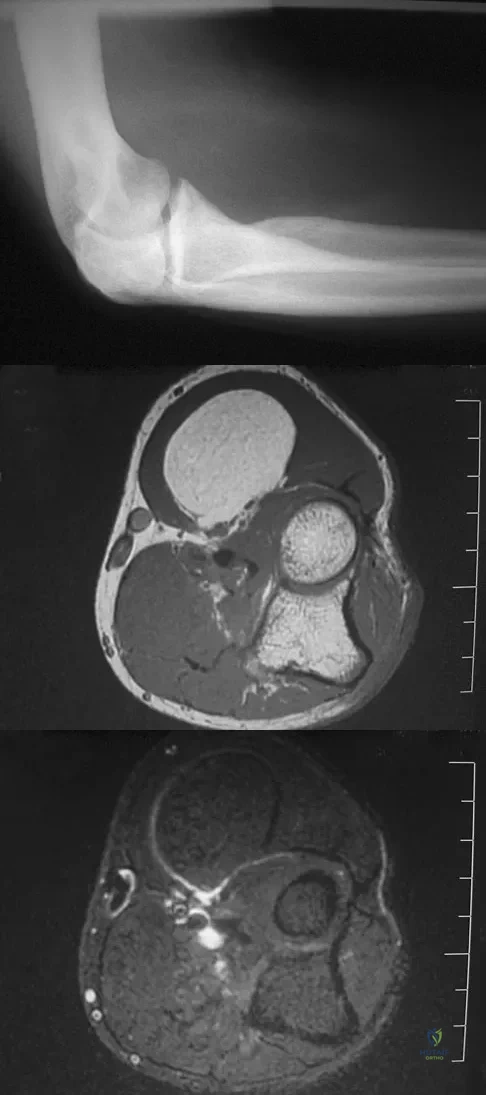

Question 6High Yield

A 55-year-old man sustained an elbow dislocation in a fall. Postreduction radiographs are shown in Figures 40a and 40b. What is the best course of management?

Explanation

Question 19High Yield

A 33-year-old man reports an enlarging painful soft-tissue mass in his right forearm. A radiograph and MRI scans are shown in Figures 45a through 45c. Treatment should consist of

Explanation